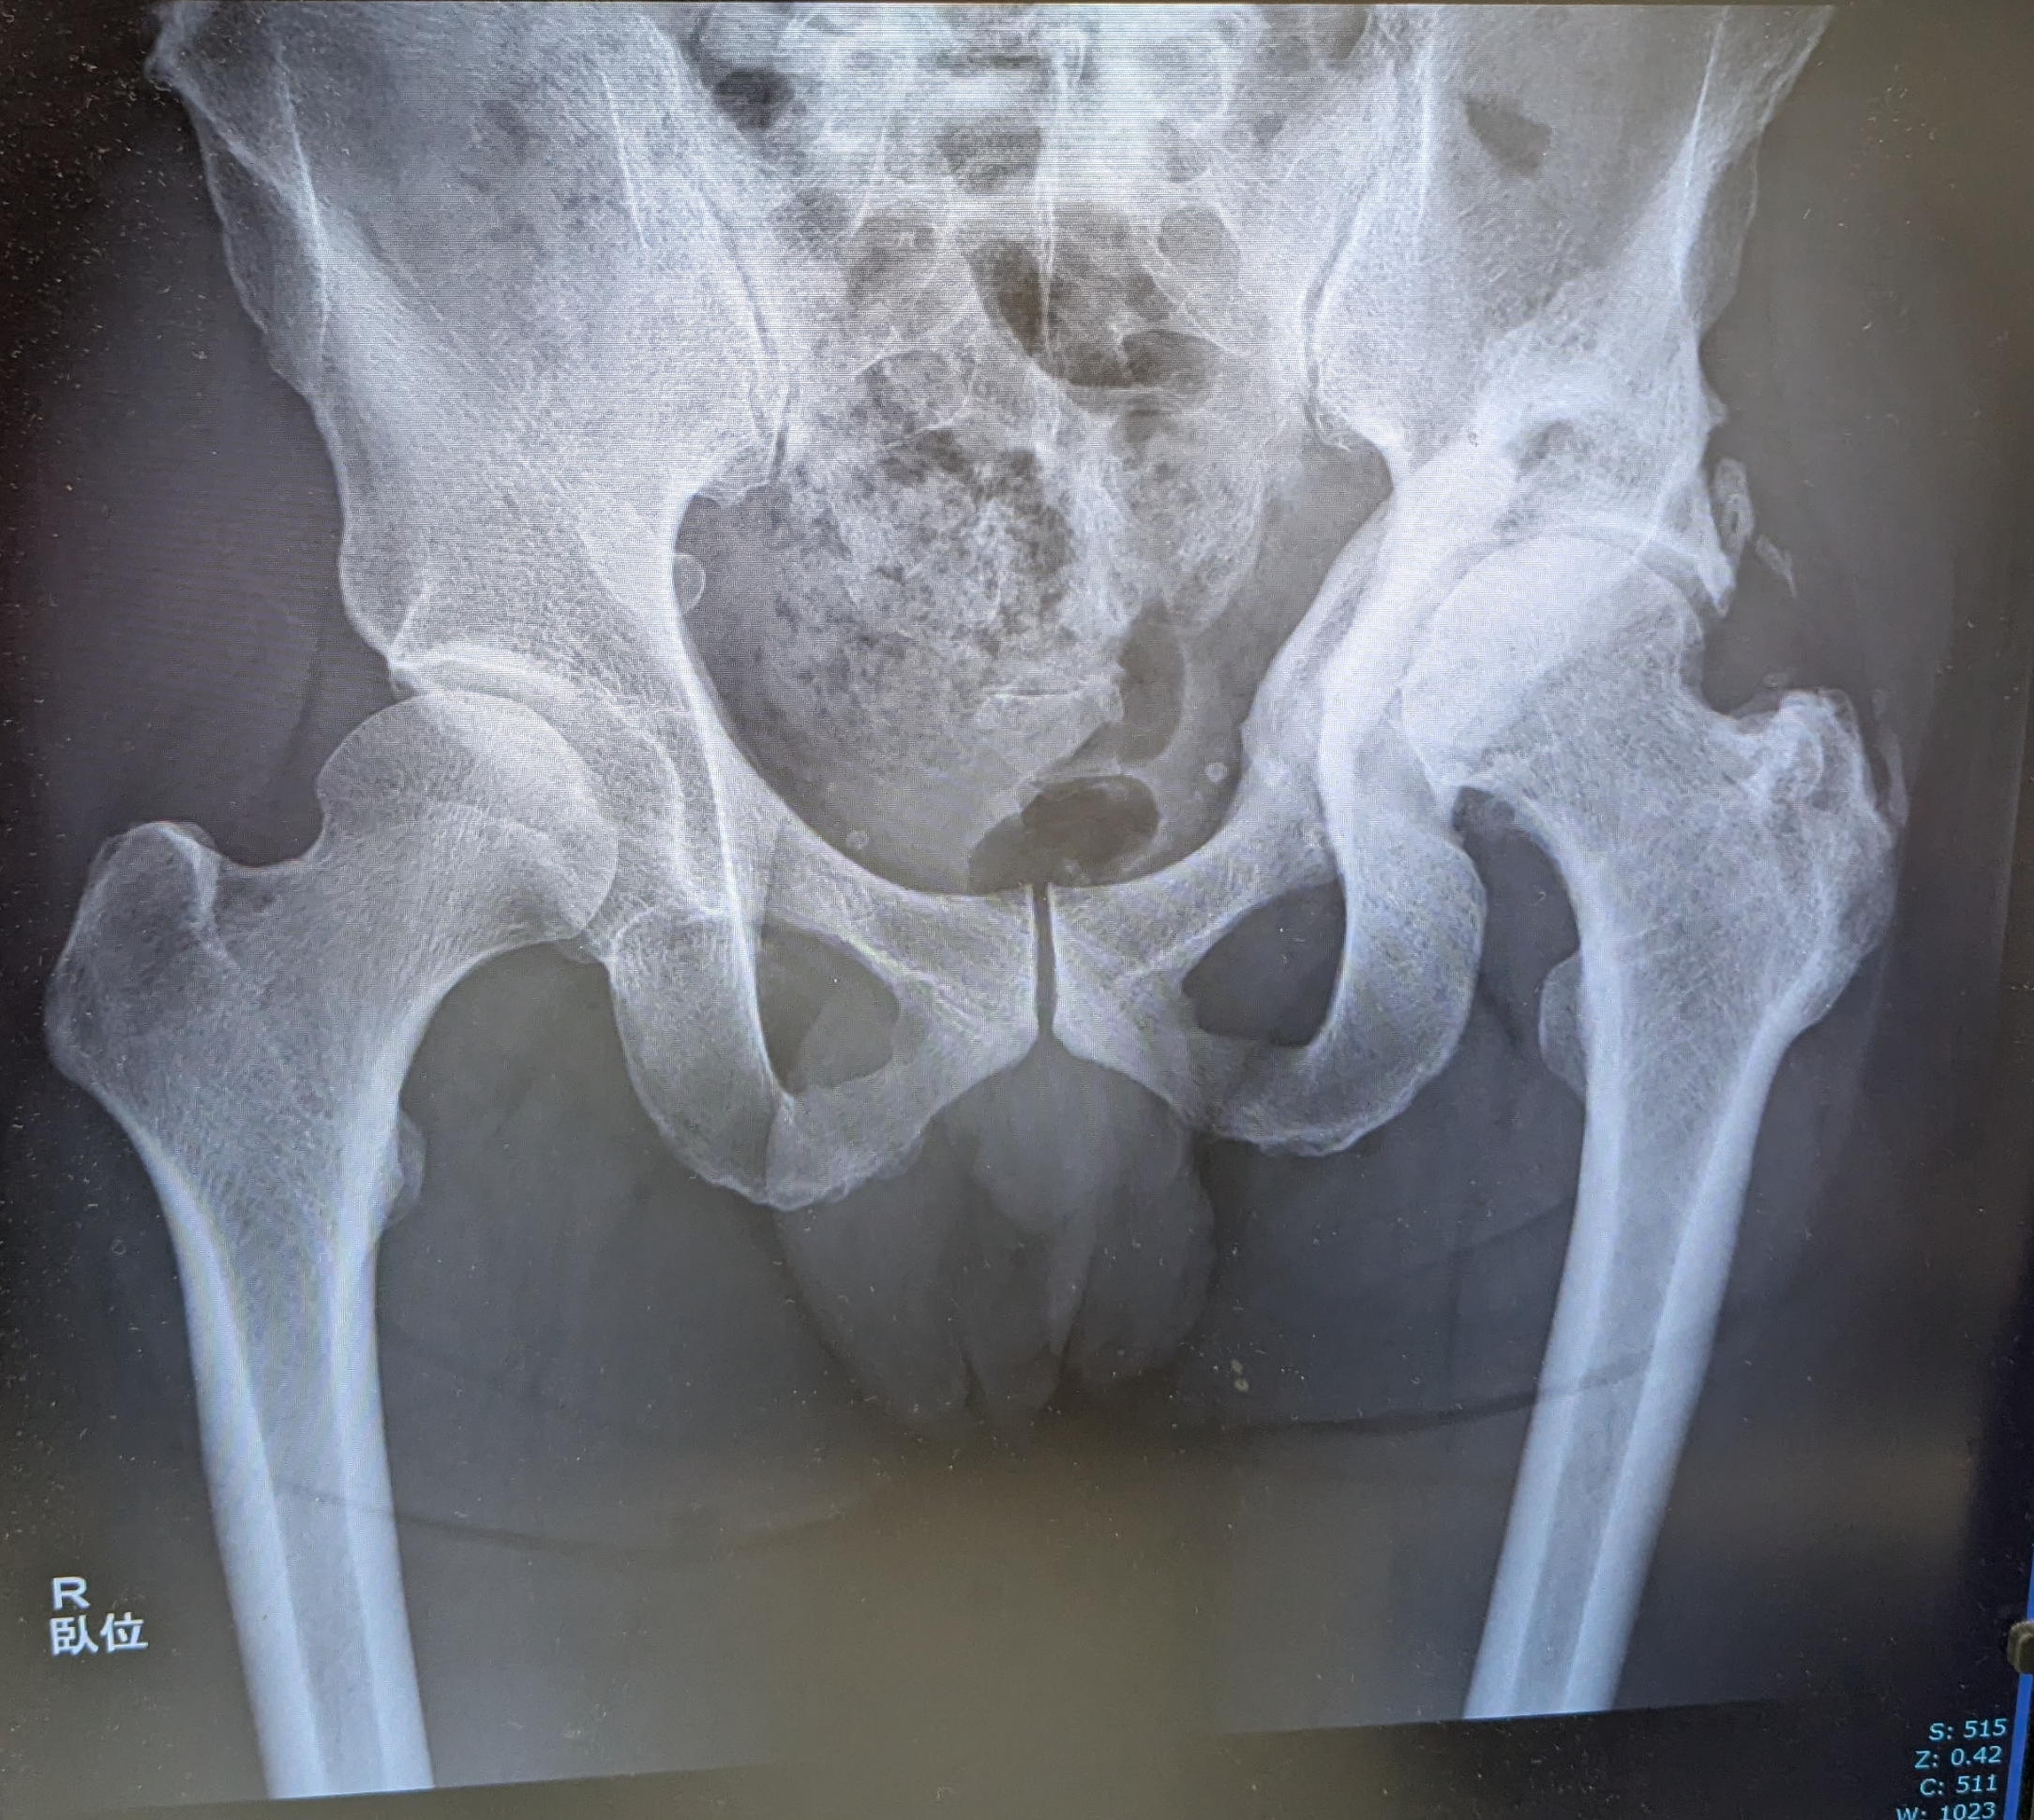

レントゲンは直ぐに呼ばれて、臥位と立位で合計3枚撮影。

- 異所性骨化巣の再発はなし

- 2回手術してるので多少は筋肉落ちてしまってヒザの力抜けることも。足を10秒上げて下ろしてを10分30セットを1カ月くらいやってみると、だいぶ膝上の筋肉ついてきて改善してくるのではないかと思います、と。